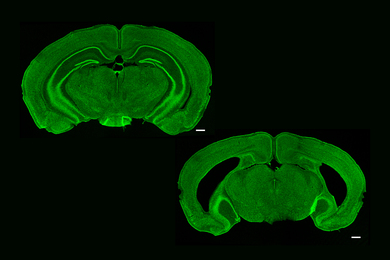

Research reveals cells that span brain hemispheres to coordinate activity in visual processing centers, shows Alzheimer’s degrades their structure and function.

To quickly express learning and memory genes, brain cells snap both strands of DNA in many more places and cell types than previously realized, a new study shows.